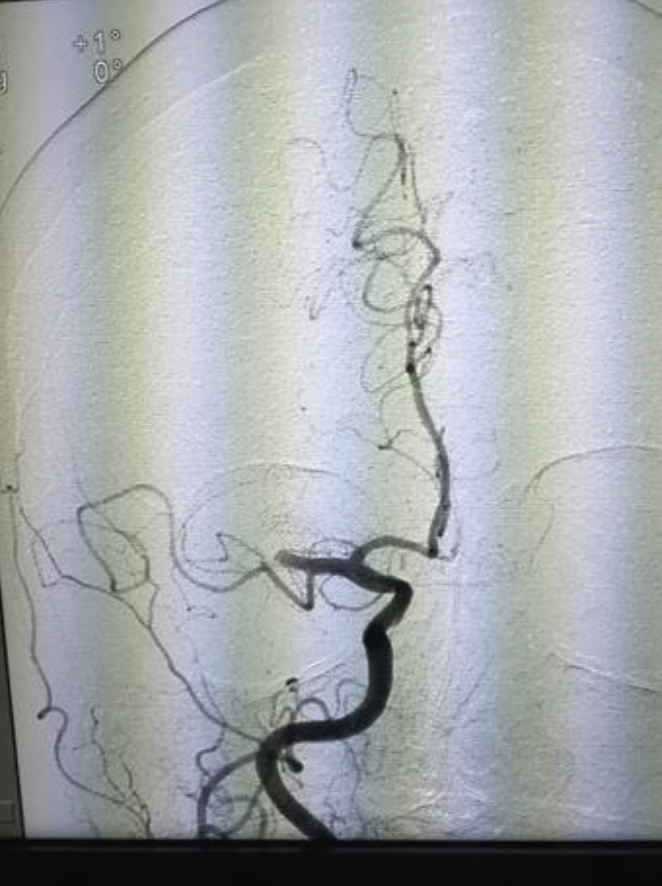

La neurocirugía endovascular es el procedimiento que seguimos los neurocirujanos para la reparación de los vasos sanguíneos, por medio de métodos minimamente invasivos. De manera más amplia consiste en un conjunto de procedimeintos para el dignóstico y tratamiento de enfermedades del sistema nervioso.

Así, la neurocirugía endovascular permite resolver eficazmente las afectaciones presentadas; se realiza por medio de la introducción de un catéter que viaja hacia el cerebro y permite llegar a la lesión para tratarla, sin necesidad de hacer una intervención quirúrgica “tradicional”, lo cual ayuda a evitar otras complicaciones y al paciente le permite una recuperación más rápida, sin necesidad de permanecer en el hospital por muchos días.